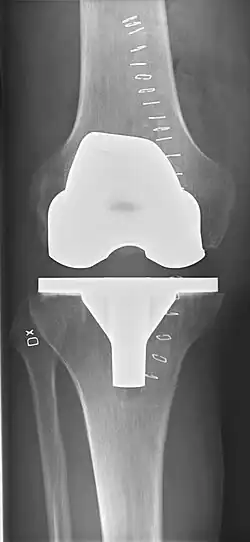

Knee replacement, also known as knee arthroplasty, is a surgical procedure to replace the weight-bearing surfaces of the knee joint to relieve pain and disability, most commonly offered when joint pain is not diminished by conservative sources.[1][2] It may also be performed for other knee diseases, such as rheumatoid arthritis. In patients with severe deformity from advanced rheumatoid arthritis, trauma, or long-standing osteoarthritis, the surgery may be more complicated and carry higher risk. Osteoporosis does not typically cause knee pain, deformity, or inflammation, and is not a reason to perform knee replacement.

Knee replacement surgery can be performed as a partial or a total knee replacement.[3] In general, the surgery consists of replacing the diseased or damaged joint surfaces of the knee with metal and plastic components shaped to allow continued motion of the knee.

- FFC: frontal femoral component angle. It is typically regarded as optimal when being 2–7° in valgus.[63]

- FTC: frontal tibial component angle, which is regarded as optimal when being at a right angle. A varus position of more than 3° has generally been found to increase the failure rate of the prosthesis.[63] -

- Anterior femoral notching (the femoral component causing reduced thickness of the distal femur anteriorly), seems to cause an increased risk of fractures when exceeding about 3 mm.[64]

- LTC: lateral (or sagittal) tibial component angle, which is ideally positioned so that the tibia is 0–7° flexed compared to at a right angle with the tibial plate.[63]